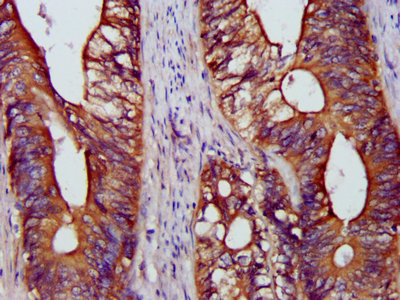

IHC image of CSB-PA03425A0Rb diluted at 1:1200 and staining in paraffin-embedded human colon cancer performed on a Leica BondTM system. After dewaxing and hydration, antigen retrieval was mediated by high pressure in a citrate buffer (pH 6.0). Section was blocked with 10% normal goat serum 30min at RT. Then primary antibody (1% BSA) was incubated at 4°C overnight. The primary is detected by a biotinylated secondary antibody and visualized using an HRP conjugated SP system.